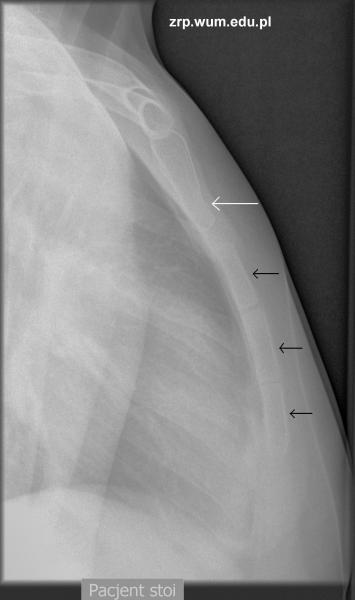

Przypadek 31: 14-letni pacjent, w trakcie przewlekłej sterydoterapii z powodu zespołu nerczycowego, zgłosił się do IP z powodu urazu okolicy mostka w trakcie ćwiczeń fizycznych. Od tej pory zgłasza ból tej okolicy.

Rozpoznanie: W badaniu RTG uwidoczniono złamanie dolnej częsci rękojeści mostka - widoczne ugięcie przedniej krawędzi rękojeści (biała strzałka). Poza tym widoczne prawidłowe jądra kostnienia mostka (czarne strzałki).